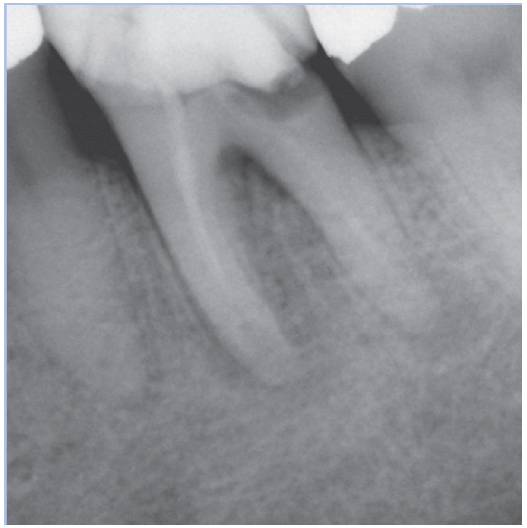

Before

Before Root Canal treatment